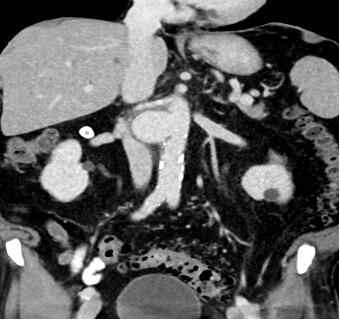

The patient was known for chronic myeloid leukemia, a prior episode of urothelial carcinoma, the presence of multiple renal cysts, and the diagnosis of a saccular juxtarenal aortic aneurysm since October 2021, which has been subject to annual surveillance. The most recent assessment took place five days before the patient presented at our emergency department and showed a stable saccular aortic aneurysm measuring 4.8 cm x 2.7 cm, using ultrasound. Laboratory findings revealed a slightly elevated C-reactive protein (23 mg/l) while white blood cell counts remained within the normal range. Hemoglobin was 9.4 g/dl.

Given the patient's unexplained symptoms, an abdominal CT scan was performed:

The CT scan together with the clinical symptoms confirmed the suspicion of a symptomatic aortic aneurysm necessitating immediate intervention. There was suspicion on the CT scan for an aorto-duodenal fistula. The surgical procedure performed, was an open replacement of the aorta due to the juxtarenal location of the aneurysm and the suspected presence of an aorto-duodenal fistula. A vascular surgeon, assisted by a visceral surgeon, performed the surgery. During the surgery, no evidence of an aorto-duodenal fistula was identified, leading to the decision to replace the juxtarenal aorta with a Dacron interposition Graft. Due to positive blood culture results in the perioperative period, the patient received a long-term course of antibiotic treatment. The patient, who made nonetheless a satisfactory recovery and was discharged two weeks following the surgery, rejected our suggestion of a re-laparotomy for more radical aneurysmal sac debridement and omentoplasty given the high suspicion of a mycotic aneurysm. A PET-CT scan performed six months after the surgery, revealed a graft infection. Despite this finding, the patient expressed unwillingness to undergo further surgical intervention. At the time of publication, the patient is still alive under suppressive antibiotic regimen.

In this case, making the correct diagnosis was a challenge given the stable aneurysm dimensions in comparison to the previous imaging and due to the atypical clinical presentation. The suspicion of an aorto-duodenal fistula on CT scan prompted an open surgical approach. Due to the unfavorable anatomy for an EVAR, due to the very short infrarenal aortic neck, the possible strategy of a bridging procedure was not an option.